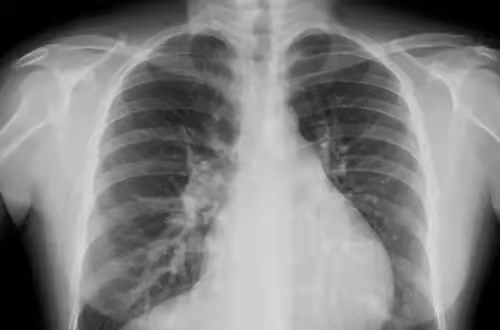

X线检查

X线检查把面包压扁看

原理简介

人体内部组织的密度不同,所以射线穿过身体时有些地方能穿透,有些地方不能穿透。比如肺被穿透后,在X线片上就是黒的,因为它没有阻挡,胶片能够全部曝光,所以呈现出来是黑的。而骨骼不容易穿透,显示出来就是白的。

应用

主要看密度,擅长骨折、肺脏病变

优点

作用广、快捷、检查费用低;

缺点

受制于深浅组织的影像相互重叠和隐藏,有时需要多次多角度拍片才能看清楚;

影像举例

dr在彩超什么意思一文搞懂X线、CT、MR、彩超检查的区别_https://www.jmylbn.com_新闻资讯_第10张

胸片能够显现我们的肺、心脏、纵膈、气管,这么多器官都在一张片子上,所有器官的影像前后压缩,变成了一张平片。所以,X线片是很多器官重叠在一起。

但是,如果肺部显示有阴影,是肺结核?肺炎?还是肿瘤?X线是不能辨别的。

为了补X线的不足CT检查技术就应运而生!